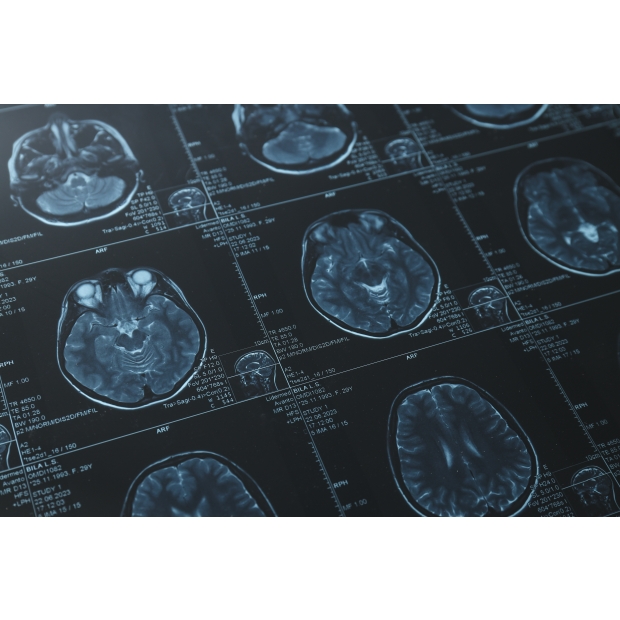

醫學影像AI軟體開發

利用獨創之AI技術針對多類型腦腫瘤(聽神經瘤、腦膜瘤、以及腦轉移瘤)進行術前磁振造影腦瘤自動圈註,給予客觀且準確的腦瘤體積定量分析。